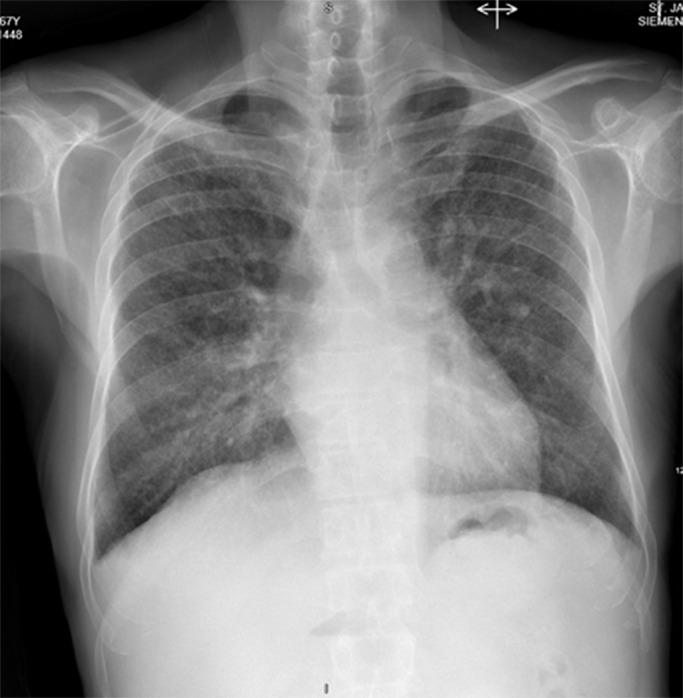

This is the first case report detailing co-infection with both PJP and disseminated histoplasmosis in a patient without HIV infection, and it highlights the immune-suppressive potential of poorly controlled diabetes and liver cirrhosis https://bit.ly/4dXUOX4.